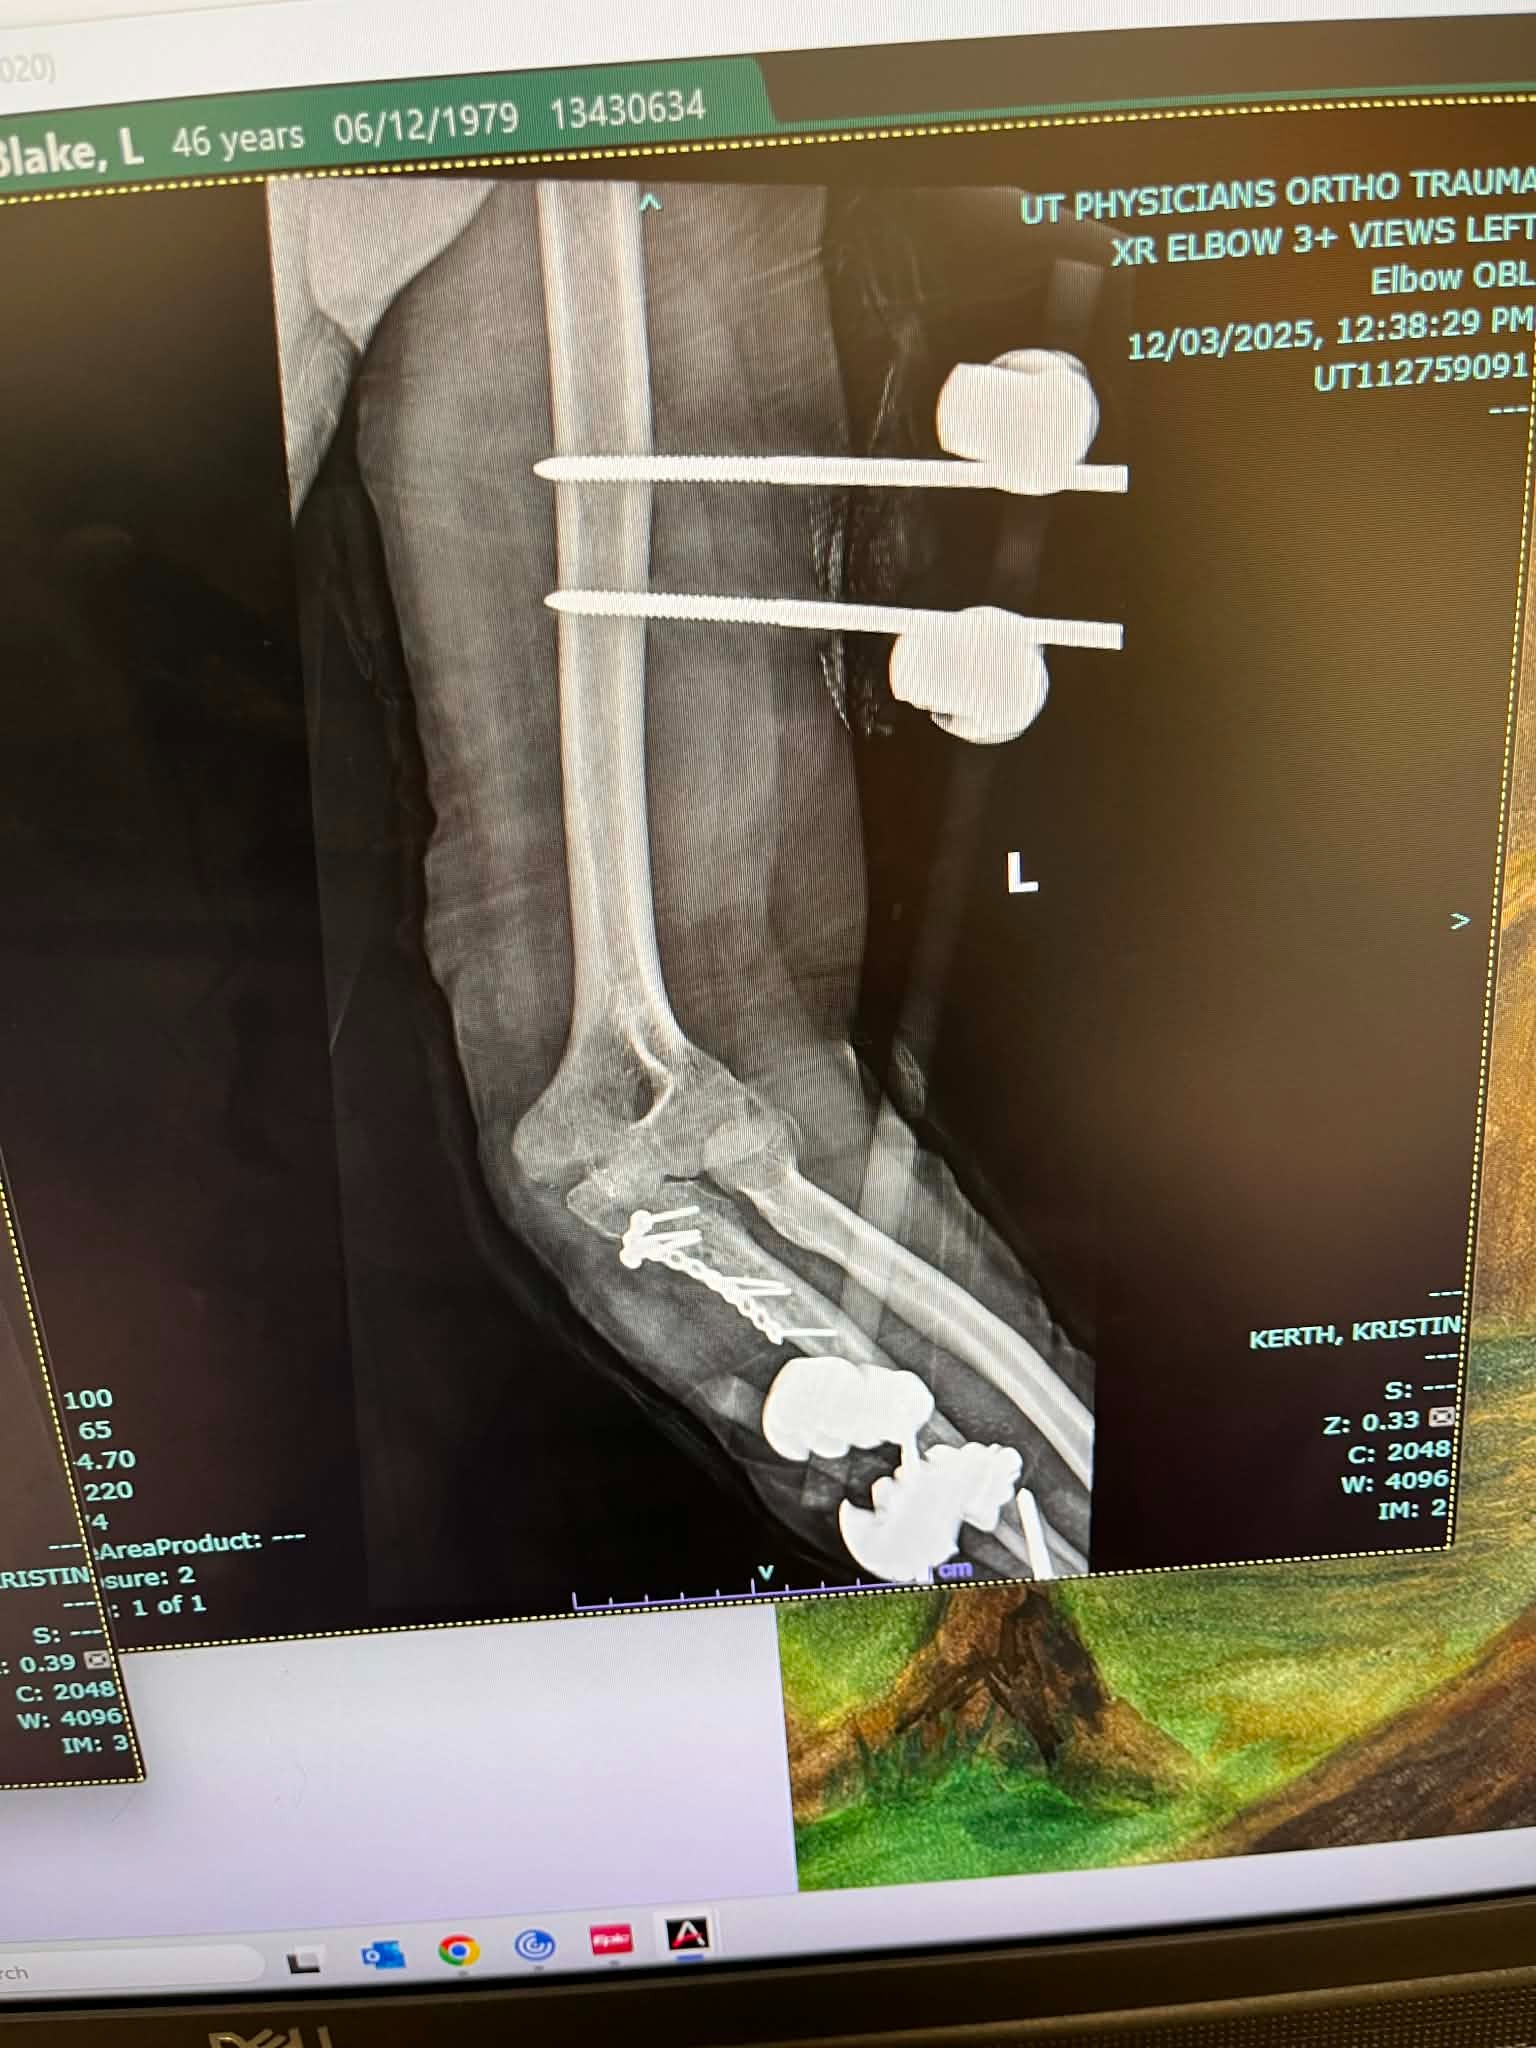

Since the accident, Blake has undergone four surgeries and is still in the long process of recovery. After the second surgery, he developed a staph infection when some of the hardware in his elbow poked through his skin. He spent five days in the hospital, had a PICC line and portable IV for a month, and had a nurse visit daily to administer medications and clean his wounds. His fourth surgery involved removing most of the hardware, as the staph infection was clinging to the metal. Now, Blake has two metal rods on the outside of his arm held in place by six screws, and his road to recovery is far from over. On top of the physical pain and uncertainty, Blake has been unable to work for six months, which has made it even more difficult to cover mounting medical bills and everyday expenses.